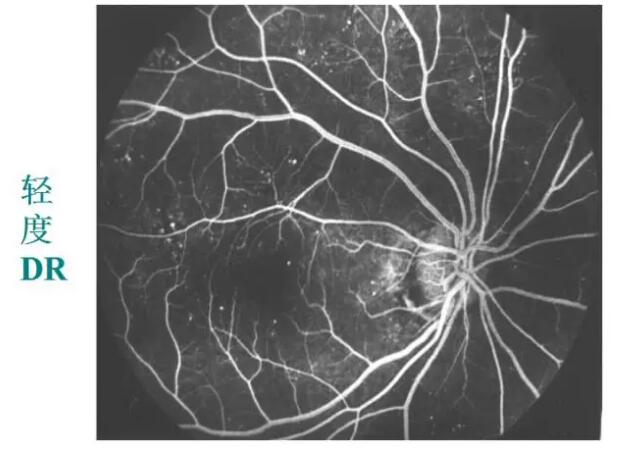

【导读】人的眼球后面有一布满微血管的薄膜即视网膜,对于高血糖与高血压患者而言,其视网膜上的微血管容易出现扭曲变形甚至破裂出血。尤其是长期、慢性高血糖导致的视网膜病变:出血、水肿、渗出、视网膜脱离等严重损害视力。

人的眼球后面有一布满微血管的薄膜即视网膜,对于高血糖与高血压患者而言,其视网膜上的微血管容易出现扭曲变形甚至破裂出血。尤其是长期、慢性高血糖导致的视网膜病变:出血、水肿、渗出、视网膜脱离等严重损害视力。

糖网病的眼底表现

微血管瘤

出血斑

渗出

视网膜静脉扩张、动脉变细、小血管闭塞

新生血管

玻璃体积血

牵拉性视网膜脱离

眼底荧光血管造影:更清楚、更敏锐